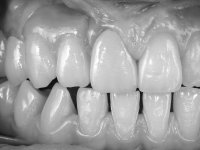

Fixed partial denture between teeth 15 and 11, using teeth 14, 13 and 11 as abutments. Teeth 12 and 15 were planned as ovoid pontics. The framework material chosen was zirconia and the veneering ceramics should have a gum-shade component to rehabilitate the soft-tissues.

After the root canal treatment of tooth 11, dental impressions were taken to do a fixed provisional (reinforced) acrylic prosthesis. The provisional bridge included an acrylic component with a gum-shade color, to evaluate the integration of the treatment plan, in relation to function and esthetics. The preparation of teeth 14 and 13 were minimal invasive, with supra-gingival finishing lines, preserving enamel at its uttermost. Tooth 11 was prepared in a conventional way, with an intra-sulcular margin. The provisional bridge was rebased intra-oral with an autopolymerized acrylic. After 4 weeks, a dental impression with a double mixture technique was done. In the dental lab, CAD-CAM technology was used to produce a zirconia framework. In the provisional bridge, it was noted by the patient, and by ourselves, the need for symmetry in the dimensions and shape of the teeth, in relation to their homologues of the 2nd quadrant. Accordingly, a mirror effect was selected in the CAD design of the framework, to mimic in the prosthetic structure the dimensions and shape of the homologous natural teeth. Framework design included also a small zirconia wing covering the palatal surface of the non-prep tooth 21. This wing serves as an additional support and, simultaneously, avoids an eventual occurrence of a future diastema between central incisors. Color selection of teeth and soft-tissues was done by the ceramist in the dental office. After evaluation and approval of the prosthetic work placed in mouth, the dental bridge was bonded. This bonding procedure was optimized by the addition of a zirconia liner in the inner surface of the framework and in the internal surface of the wing. This treatment proved to be esthetically acceptable and functionally able, with a strong contribution to the patient’s self-esteem.